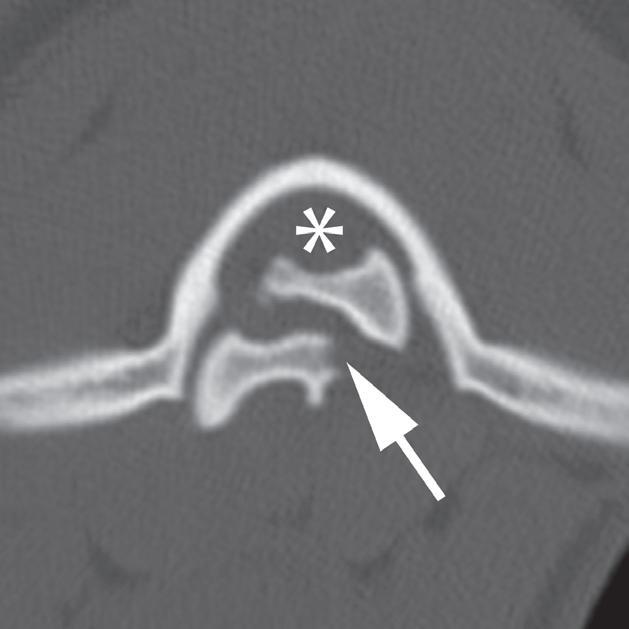

Badanie wykonano u 2-letniej samicy owczarka australijskiego z bólem odcinka szyjnego kręgosłupa, ale bez deficytów neurologicznych, która 9 dni przed badaniem wpadła na ogrodzenie. Obrazy przedstawione na ryc. a–c ułożono od strony czaszkowej do ogonowej na poziomie zęba obrotnika (a – grot strzałki), doczaszkowej części C2 oraz środkowej części trzonu C2. Obraz na ryc. d to rekonstrukcja w płaszczyźnie strzałkowej przez linię pośrodkową, a na ryc. e zamieszczono obraz wykonany w pobliżu płaszczyzny strzałkowej obejmujący ząb obrotnika (e – grot strzałki). Widać przemieszczenie skośnego złamania trzonu kręgu obrotowego (axis) (b–f – strzałka). Przemieszczenie fragmentu złamania względem atlasu powoduje znaczne zmniejszenie średnicy kanału kręgowego (b – gwiazdka). Złamanie jest widoczne na radiogramie (g – grot strzałki), jednak poziomu zwężenia kanału kręgowego nie da się ocenić równie dokładnie jak na obrazach TK. Ze względu na upływ czasu od urazu i brak objawów neurologicznych pacjentkę leczono zachowawczo, jednak właściciel zwierzęcia nie zgłosił się na dalsze wizyty kontrolne